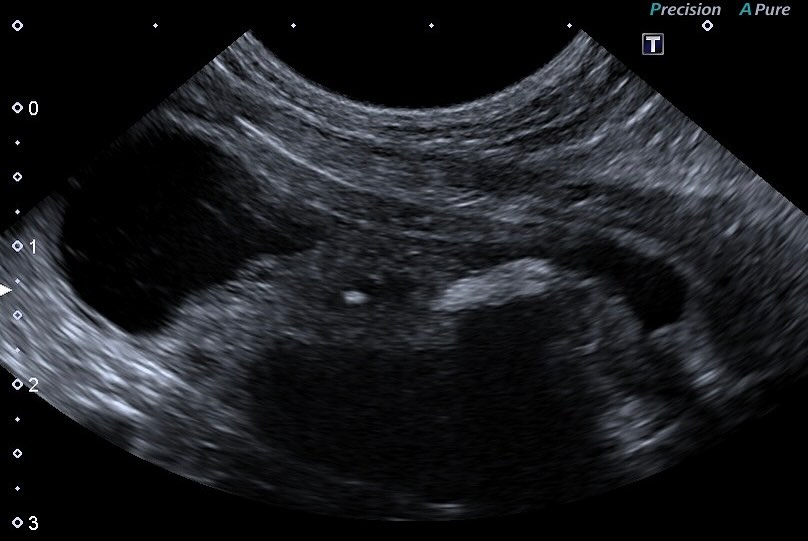

このように異常が早期に発見されるのは、検査機器の進歩やご家族の健康意識が向上しているおかげです。🐕🩺わんちゃんが元気に見えていても、やはり定期的な健康診断は大切です!見た目だけでは判断できない内部の問題を早期に発見することで、治療や対策が迅速に行え、愛するペットの健康を守ることができます。👍みなさまの大切な家族の一員であるペットのためにも、ぜひ適切な健康診断を受けさせてあげてくださいね。🌟